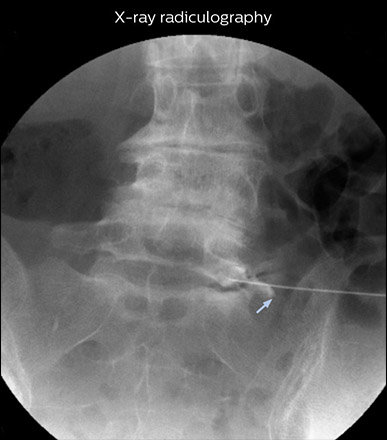

“In such case, we would then browse through axial T2-weighted MR images slice by slice and mentally reconstruct the actual situation based on both radiculography and MRI. Fortunately, NerveVIEW can now very well show nerve courses and presence of nerve compression or edema in one single image series.” “We have often seen NerveVIEW directly depict details of the nerve compression that were not observed by radiculography. Therefore, we think that with NerveVIEW we can reduce the number of invasive examinations, especially for some patients with lumbar plexus symptoms.”

“Before NerveVIEW, diagnosis by MRI alone was sometimes difficult, unless there was a strong suspicion based on clinical symptoms,” says Shoji Yabuki, MD, DMSc, Orthopedic surgeon at Fukushima Medical University School of Medicine. “This is why we routinely perform selective lumbosacral radiculography (nerve root block) and x-ray in such cases. However, radiculography can only depict nerves as far as the contrast agent reaches. When a nerve is distorted by compression, the contrast agent will not pass through this compressed area, preventing us from evaluating the full nerve compression.”

“NerveVIEW can clearly show nerve courses and presence of nerve compression. However, when multiple abnormalities are seen, it can still be hard to determine which nerve is causing the symptoms,” says Dr. Yabuki. “In our experience so far, we see abnormal findings on NerveVIEW in about 70% of elderly patients. As the pain is usually caused by only one nerve, we thus need to find the exact corresponding nerve.” “With a nerve root block, the patient's pain is improved by infiltration of local anesthesia directly around the nerve root considered to be responsible. Knowing such nerve root block findings prior to image interpretation, helps to easily recognize abnormal findings on NerveVIEW as well. In other words, without a priori knowledge, based on symptoms and/or nerve root block findings, we must be aware of the possibility of overdiagnosis.”